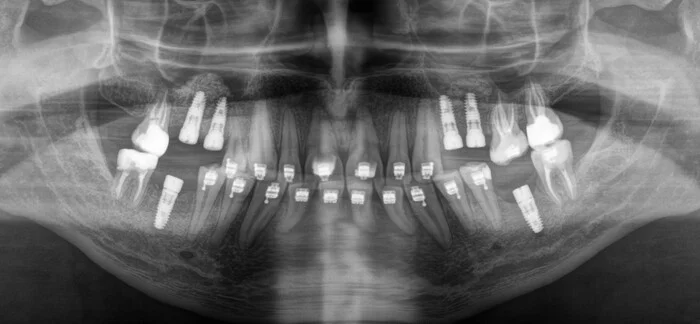

Через три с половиной месяца стоматолог-ортопед Кирилл Киселев-Тростянский может приступить к временному протезированию. Сначала с правой стороны, затем с левой. Не вижу смысла добавлять много одинаковых картинок, поэтому вот вам снимок после временного протезирования:

Временные коронки изготавливаются из нерентгеноконтрастного композитного материала, поэтому на рентгеновских снимках их не видно. Зато видны металлические абатменты, фиксирующие коронки винты и состояние графта в областях проведенных синуслифтингов и костную ткань вокруг имплантатов. Везде всё зашибись — графт интегрировался (слева полностью, справа — на финальной стадии), имплантаты, абатменты и зубы прекрасном состоянии.

Ремарка: обратите внимание на разницу в абатментах на верхней и нижней челюстей. На нижней абатменты, вроде как, заполняют всю шахту имплантатов, в то время как шахты верхних имплантатов кажутся пустыми. Дело в том, что нижние абатменты предназначены для протезирования одиночных зубов и имеют антиротационный элемент (индекс, шестигранник), в то время как верхние абатменты шестигранного индекса не имеют. Другими словами, это не баг, а фича.